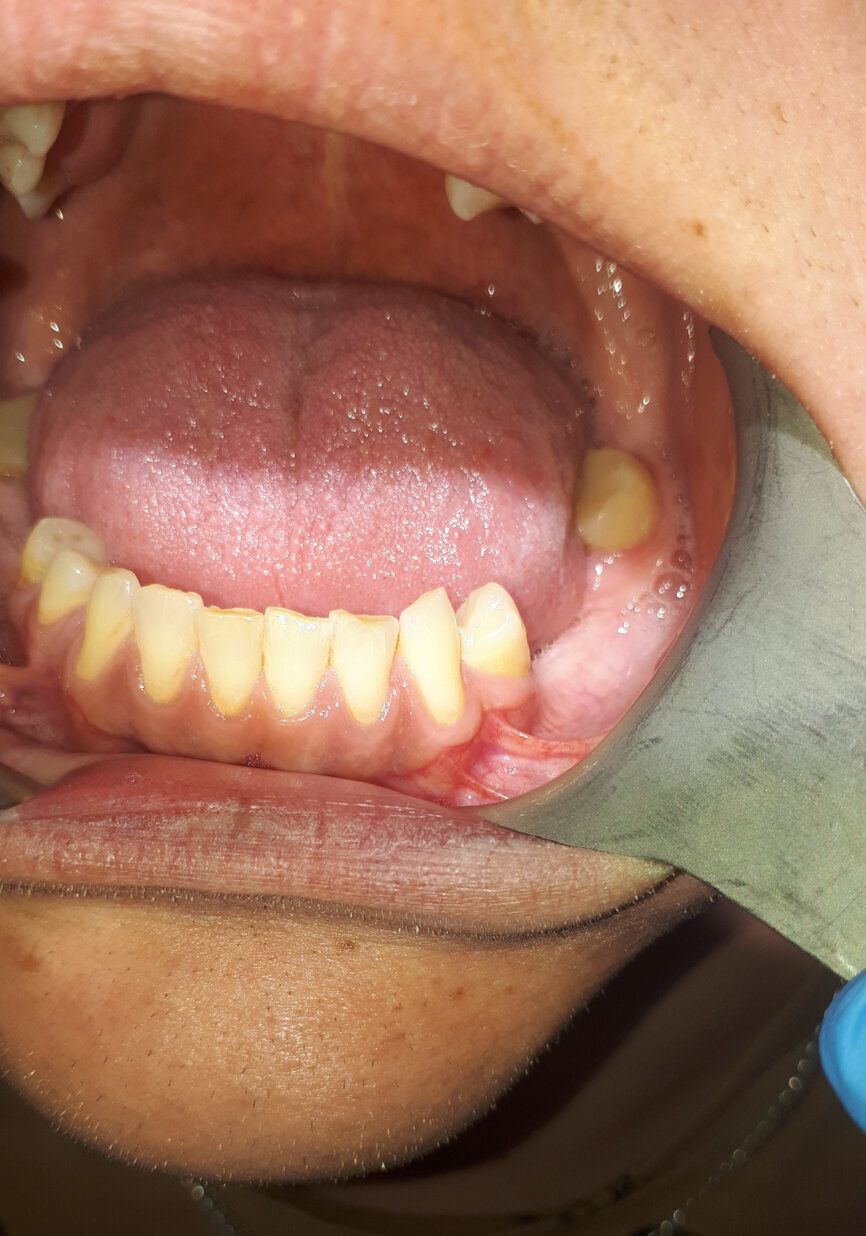

Po 4 tygodniach od zabiegu otrzymano wynik badania histopatologicznego, opisujący ścianę torbieli wyścieloną nabłonkiem wielowarstwowym płaskim, bez cech atypii, bez przydatków skóry (Ryc. 2). Na podstawie tego wyniku w zestawieniu z danymi klinicznymi postawiono rozpoznanie: torbiel naskórkowa zlokalizowana śródkostnie.

Ryc. 2: Preparat histopatologiczny, powiększenie x10, barwienie hematoksylina i eozyna.